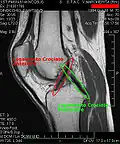

МРТ коленного сустава.

Крестообразные связки.

Применяются физикальные методы исследования: осмотр, пальпация, а также сбор анамнеза. Из инструментальных методов для визуализации изменений анатомических структур сустава большое распространение получило МР-исследование. Для оценки целостности и структуры костей, формирующих сустав, предпочтение отдаётся рентгенографии и компьютерной томографии. В настоящее время для диагностики применяют также артроскопию.

При застарелых разрывах связок симптом «выдвижного ящика» может стать нечётким вследствие развития вокруг места разрыва жировой клетчатки, которая отчасти стабилизирует коленный сустав. Диагноз уточняют при рентгенологическом исследовании. Иногда приходится прибегать к введению контраста в полость коленного сустава или к компьютерной или магнито-резонансной томографии. При необходимости проводят артроскопию: вводят зонд в полость сустава и осматривают сустав изнутри. В качестве первой помощи необходимо обезболить место повреждения, обездвижить коленный сустав с помощью шины и доставить пострадавшего в травмпункт.